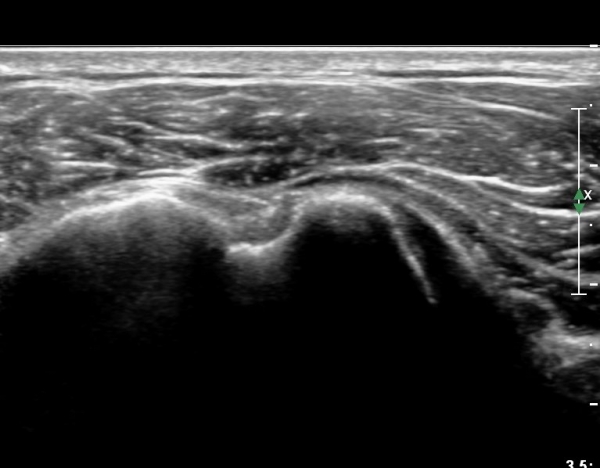

ÃÊÀ½ÆÄ ¼Ò°ß :  ÀÌµÎ¹Ú±Ù°Ç È¾´Ü¸é°Ë»ç¿Í ±Ø»ê°Ç Á¾´Ü¸é°Ë»ç¿¡¼­  ƯÀÌ ¼Ò°ß ¾øÀ½(»çÁø 1, 2).

°ß°©ÇÏ±Ù°Ç ÇϺΠÁ¾´Ü¸é°Ë»ç¿Í Ⱦ´Ü¸é°Ë»ç °ß°©Çϱٰdz»  ¼®È¸È­ À½¿µÀÌ  °üÂûµÈ´Ù(»çÁø 3, 4).